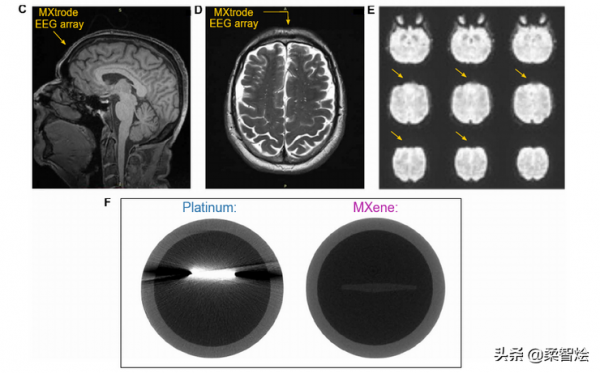

“電極以平面或三維形式製造,並應用於志願者的面板,用於記錄大腦活動的腦電圖、測量肌肉活動的肌電圖、監測心臟活動的心電圖和繪製眼球運動的眼電圖。電極陣列還可以植入豬和大鼠體內,用於術中監測和大腦刺激,並顯示出與磁共振和計算機斷層掃描成像的相容性。這些靈活的介面在多尺度表皮感測和神經調節方面具有潛在的臨床應用價值。”